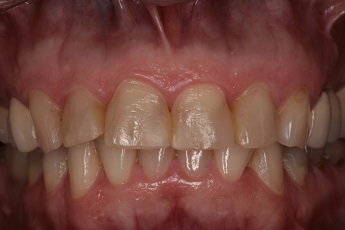

![]() |

Foto 27, 28: Stav před a po kompletním ošetření rekonstrukci ortodontické vady fixním můstkem.